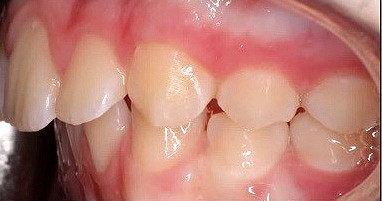

Neunjähriger Patient mit deutlich vergrößertem Overjet aufgrund eines Distalbisses in Kombination mit einer Protrusion der Oberkieferfront. Habits bzw. myofunktionelle Aspekte wurden adressiert. Die Behandlung erfolgte mit einem Invisalign-Schienensatz (56 Aligner) mit Precsion Wings im Rahmen einer Frühbehandlung zur Prophylaxe eines Frontzahntraumas.

Klinisches Fallbeispiel 2 (Abb. 2a–y)

Distalbiss und tiefer Biss bei einem zwölfjährigen Mädchen. Die Behandlung erfolgte mit Invisalign und Precision Wings. Insgesamt waren zwei Schienensätze notwendig. Die Gesamtbehandlung dauerte 18 Monate.Bei der Planung des ClinCheck wurde der tiefe Biss vorwiegend über eine Intrusion der Unterkieferfront behoben, um die Lachlinie der Patientin nicht negativ zu beeinflussen. Die Oberkieferfront wurde nur retrudiert, jedoch vertikal nicht intrudiert. Während der Phase des Mandibular Advancement wurde die Wirkung der Precision Wings durch den Einsatz von Klasse II-Gummizügen unterstützt. Schlussendlich wurde auch der hängenden Okklusionsebene durch eine einseitige Intrusion der Molaren im ersten Quadranten Rechnung getragen.